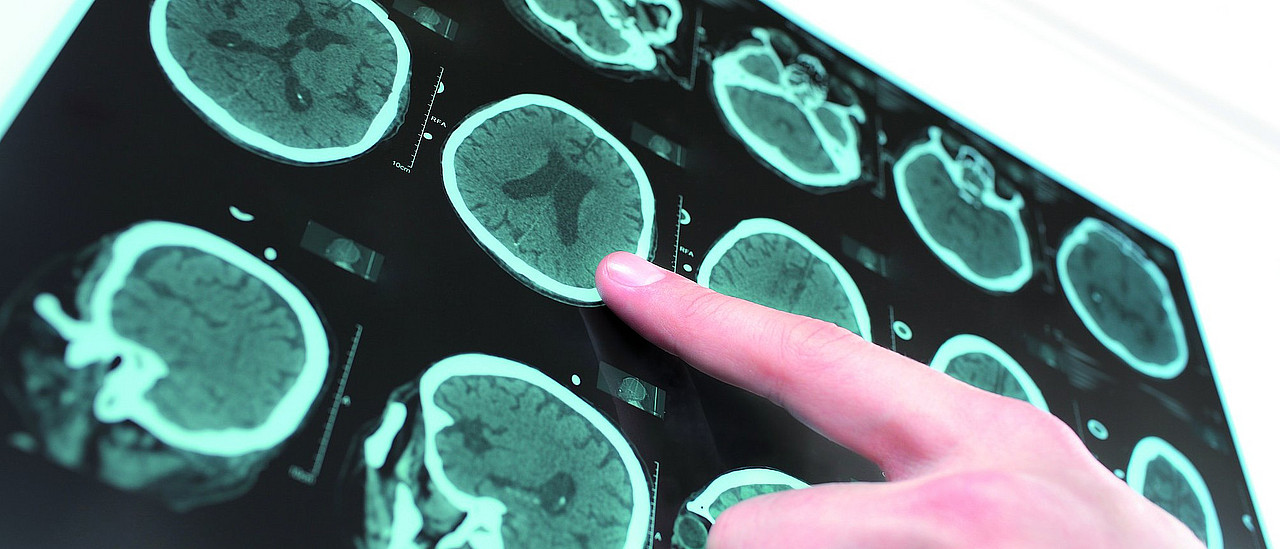

In der Neuroradiologie ist es noch einen Tick komplizierter. Denn das Gehirn ist in einer harten Nuss unseren Schädeln – eingeschlossen. Aufmachen und Reingucken ist da nicht so ohne weiteres möglich. Antonio Schuller, Medizinisch-Technischer Radiologie-Assistent (MTRA) und EDV-Crack an unserem Regensburger Institut für Neuroradiologie, zeigt mir am Computer, worum es geht. Auf einem Monitor sehe ich zwei Schädel im Querschnitt, einmal von vorne, einmal von oben. „Die Bildgebung in einer modernen Neuroradiologie ist heute vollständig digital. Das heißt, die Bilder, die gemacht werden, werden nur noch in elektronischer Form aufgenommen, gespeichert und bereitgestellt“ sagt Schuller.

Bei modernen radiologischen Verfahren werden viele digitale Einzelbilder in hauchdünnen Abständen – beim CT in Körperlängsrichtung, beim MRT auch entlang einer beliebigen Achse durch den Körper – aufgenommen. Im Rechner werden die einzelnen Schichtbilder berechnet und dann zusammengesetzt. Schuller klickt auf eine Taste und der eine Schädelschnitt fängt an sich zu verändern. „Der direkte Nutzen – die Intelligenz – der Verfahren betrifft nicht nur die einfachere Archivierung. Die Bildinformation selbst ist viel wichtiger“ erklärt er mir. Mit der Maus steuert er den Bildablauf und sieht sich Schicht für Schicht die Aufnahmen des Gehirns an – wie in einem Film, den er vor- und zurücklaufen lassen kann. „Hier schauen wir von oben auf den Schädel. Gleich tauchen die Augen auf und dann die Nebenhöhlen, hier der Hirnstamm …“.

Die Bilder faszinieren mich: Man kann an jede beliebige Stelle im Schädel direkt hinsteuern. „Beim alten Röntgen mussten wir noch vorher festlegen, was wir unter die Lupe nehmen wollten. Hinter Knochen kann man halt nur sehen, wenn man ein zweites Bild mit anderer Perspektive macht“, erzählt mir Schuller. Er zeigt mir, wo ich hinschauen muss. Weiße, graue und schwarze Strukturen tauchen auf dem Bildschirm auf, werden größer, kleiner, verschwinden wieder. Es sind Knochen, Gewebe, Gefäße. Mittels Kontrastmitteln werden Blutgefäße und ihre Veränderungen sichtbar. Schuller: „Dieser kleine Knubbel ist das Problem. Bis dahin fließt Blut in der Hirnarterie, dahinter wird es im CT im wahrsten Sinne zapfenduster.“ Er schaut ernst, denn der Befund zeigt einen Gefäßverschluss, der einen schweren Schlaganfall verursachen kann.